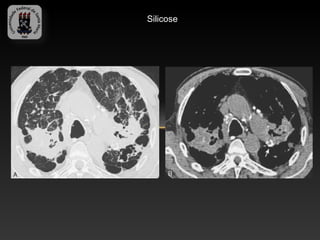

-SILICOSE E DOENÇA DO MINERADOR DE CARVÃO

-Doença fibrótica, causada por inalação de poeira que contem sílica.

-Silicose: crônica, aguda e acelerada.

-Sindrome de Caplan

-TC: nódulos de distribuição centrolobular, mais proeminentes nas

porções posteriores das regiões superiores.

-Calcificações de lifonodos hilares e mediastinais (casca de ovo)

-A progressão dos nódulos leva a fibrose maciça progressiva

(conglomerado de nódulos), cicatrizes parenquimatosas e enfisema

cicatricial.

Silicose